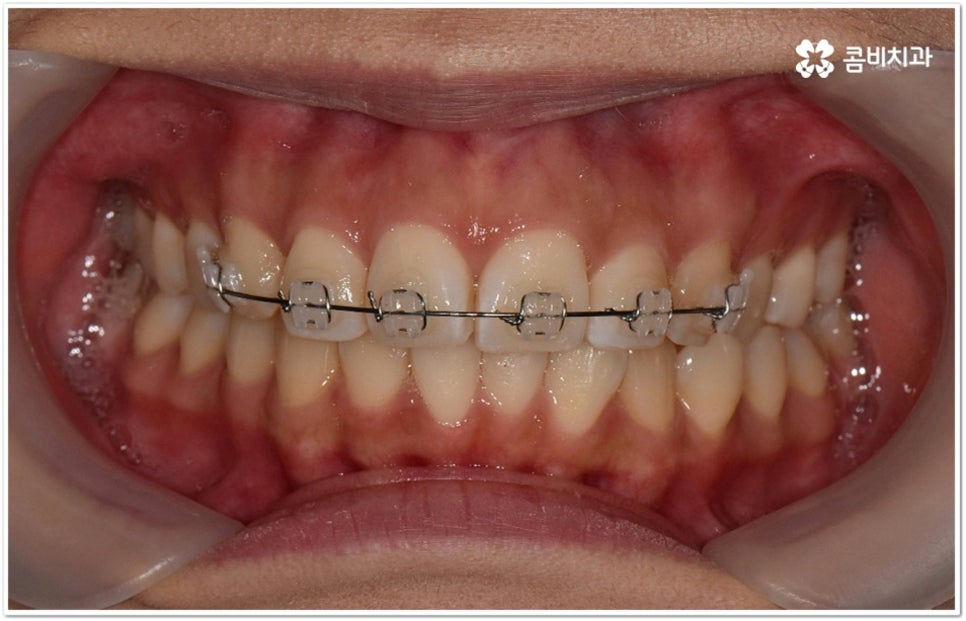

덧니의 원인에는 여러 가지가 있는데 대표적으로는 유치가 너무 일찍 빠져서 영구치가 제대로 자리를 잡지 못했거나 턱뼈의 크기와 치아 크기가 조화를 이루지 못하는 경우 등 공간이 부족한 상황을 생각해 볼 수 있어요. 덧니는 주로 송곳니가 가장 흔하나, 치열이 공간이 부족할 경우 이론적으로는 어떤 치아라도 덧니가 될 수 있어요. 이때 원인과 정도를 꼼꼼하게 파악하여 만약 해당 부위만 부분 교정이 가능하다면 덧니부분교정 치료를 할 수 있는데요. 덧니부분교정 을 이용하면 원하는 부위에만 브라켓을 부착하여 치아 이동을 시키기 때문에 전체 교정에 비해서 간편하며 치료 기간도 6~8개월 정도로 줄어들고 통증도 많이 감소될 수 있습니다. 비용적인 부담도 덜하며 (삐뚤어진 정도나 상태에 따라 다르겠지만) 보통 덧니부분교정 의 경우 비발치 과정으로 진행되기 때문에 환자분들의 입장에서는 덧니부분교정 을 많이 선호하시는 편이라고 할 수 있어요. 상황에 따라 미니스크류, 치간삭제, 악궁확장장치 등 환자에게 맞는 비발치 방법을 이용하여 도움 받을 수 있습니다.

요즘 가장 많이 쓰이는 클리피씨 장치는 이런 면에서 많은 장점을 가지고 있어요. 예전과 다른 자가 결찰 방식을 이용하기 때문에 마찰로 손실되는 교정력이 줄어들어 좀 더 적은 힘으로도 부드럽고 지속적인 치아 이동을 가능하게 하므로, 상황에 따라 다르지만 보통 6개월 정도의 기간 단축 및 이동시 초기에 느낄 수 있는 통증을 덜어준다고 할 수 있는데요. 그밖에도 치아 색상의 브라켓을 이용하여 심미성 또한 뛰어나며 상황에 따라 환자분들에게 맞게 내원 횟수도 줄여줄 수 있다고 하니 숙련된 의료진과 충분하게 상담해 보시고 신중한 선택하시길 권유드리고 있습니다.